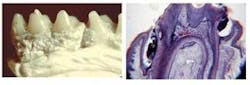

Meeting Dr. Keyes and hearing him lecture was like a coming home party for me. The title of his presentation was “A 30-year Perspective on Non-Surgical Periodontal Therapy,” and it was a historical journey. Dr. Keyes is a giant of a man who is short in physical stature, and I could barely see him as he stood behind the podium. He insisted that this particular lecture would be his last, and he became very emotional when he showed us a photo of one of his Syrian hamsters, which was very dear to his heart. Dr. Keyes showed the audience numerous slides of heavy plaque growth in periodontally healthy hamsters, which led to destruction of the periodontium. He also showed us periodontal health in the absence of heavy dental plaque on the tiny teeth of these little critters. He showed us a photo of experimentally induced periodontitis, and one of root caries in hamsters. (I wondered how he concocted a vinyl fluoride tray for a tiny Syrian hamster.)